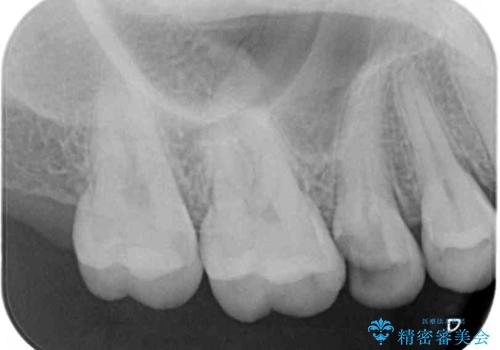

- 根管治療が必要な虫歯を放置した結果、抜歯が必要と診断されたとのことで来院された患者様です。

口腔内の状態やレントゲン写真から判断し、長期的なことを考えると抜歯が無難と思われましたが、それを承知の上で保存するための処置を行うこととしました。

まずは虫歯を除去した上で根管治療を行い、部分矯正により骨内深い位置にまで及んだ健全な部分を引っ張り出すこととしました。

その後骨形成処置を行い、治癒を待って補綴治療を行うこととしました。